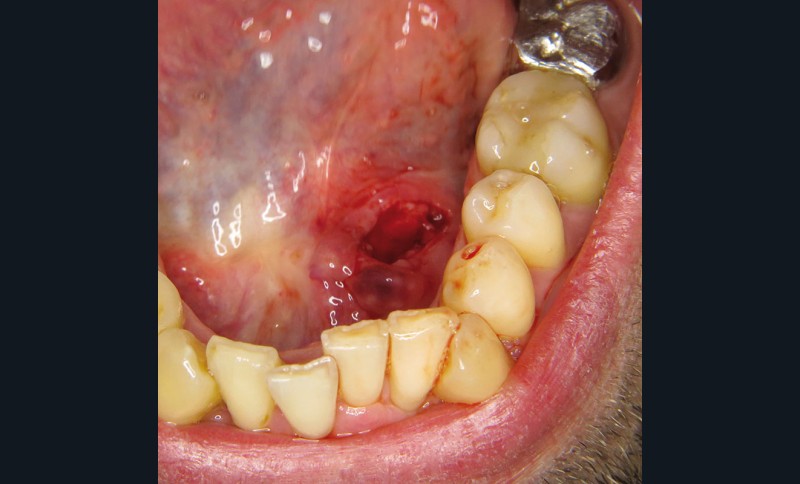

La prise en charge est chirurgicale sous anesthésie locale. Une incision du toit du nodule est réalisée (fig. 4 et 5).

La lithiase est libérée du canal aux ciseaux de Metzenbaum, ce qui permet son énucléation en un seul fragment de plus de 2 cm de grand axe (fig. 6).

Le canal n’est pas suturé, une suture du plan le plus superficiel est réalisée au Vicryl rapide 4/0.